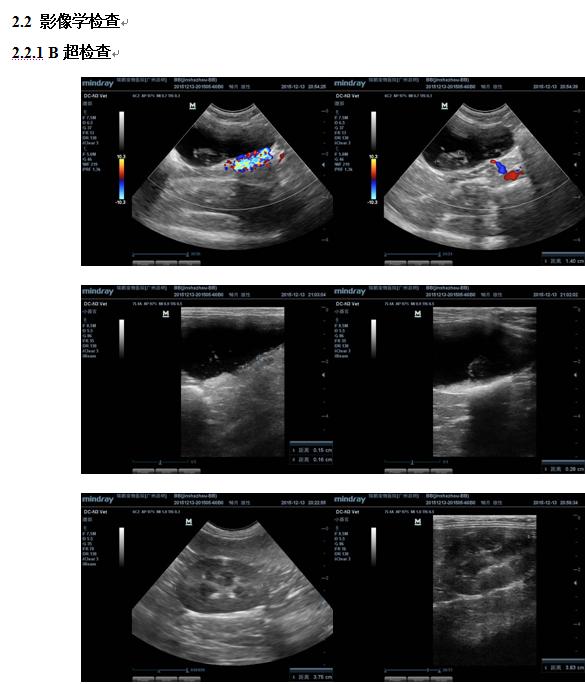

B超检查显示,膀胱充盈,部分膀胱壁不光滑,有增厚;膀胱内悬浮高回声颗粒及回声不均中低回声团块,团块回声不均,形状不规则;膀胱壁受重侧可见高回声颗粒沉积;颗粒及团块随着体位改变而移动。左右肾脏边界清晰,皮质髓质结构清晰,但形态肿大。